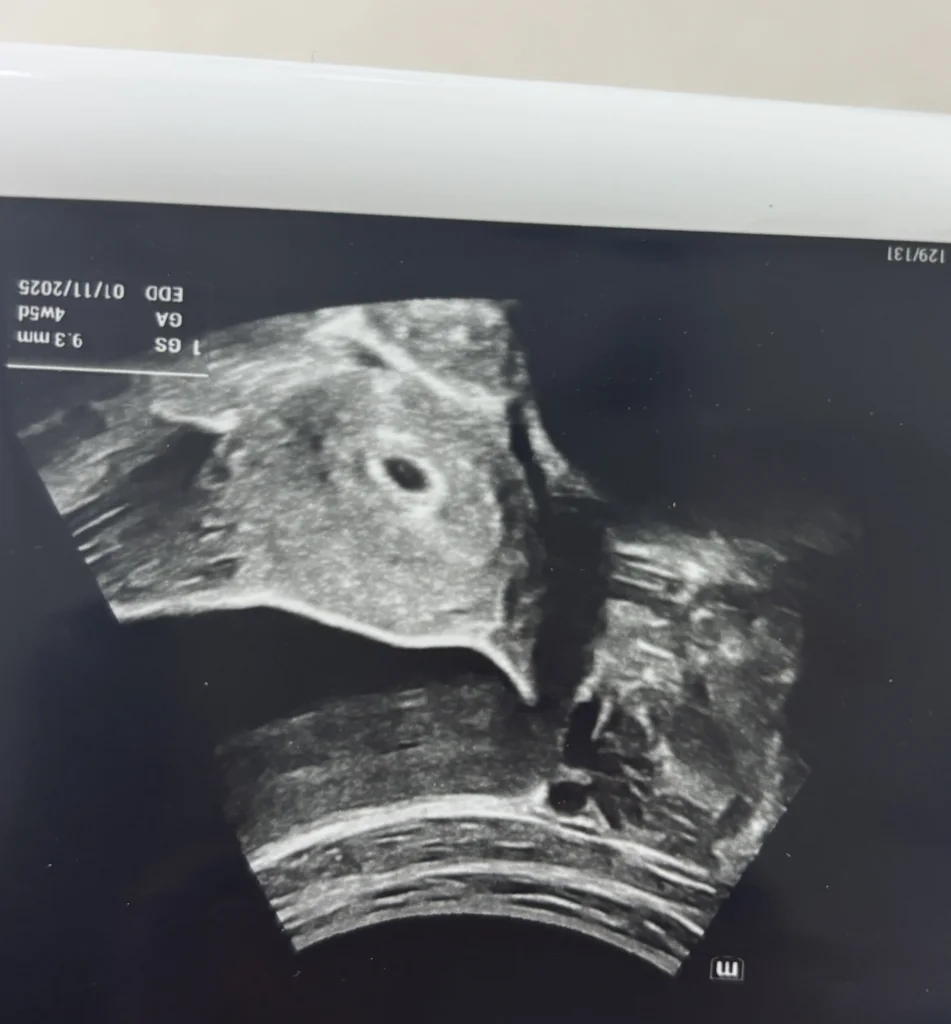

merhaba bende kasim annesi olacagim insallah test yapmisdim pozitivdi. usm da muayine oldum kese var amma cok kucuk dedi. 1 hafta sonraya yine gitmeliyim. 4 hafta 6 gun oluyor hesaplayinca. ama cok kucuk gozukdu. 1 oglum var 7 yasinda ondan sonra 2 dusuk var kan pihtisi sorunu cikti.Bakalim insallah bu kez saglikla dogar